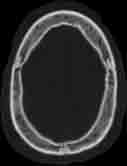

Visible Human male: Sectio transversalis 1034

CT

NMR

Pd T1 T2